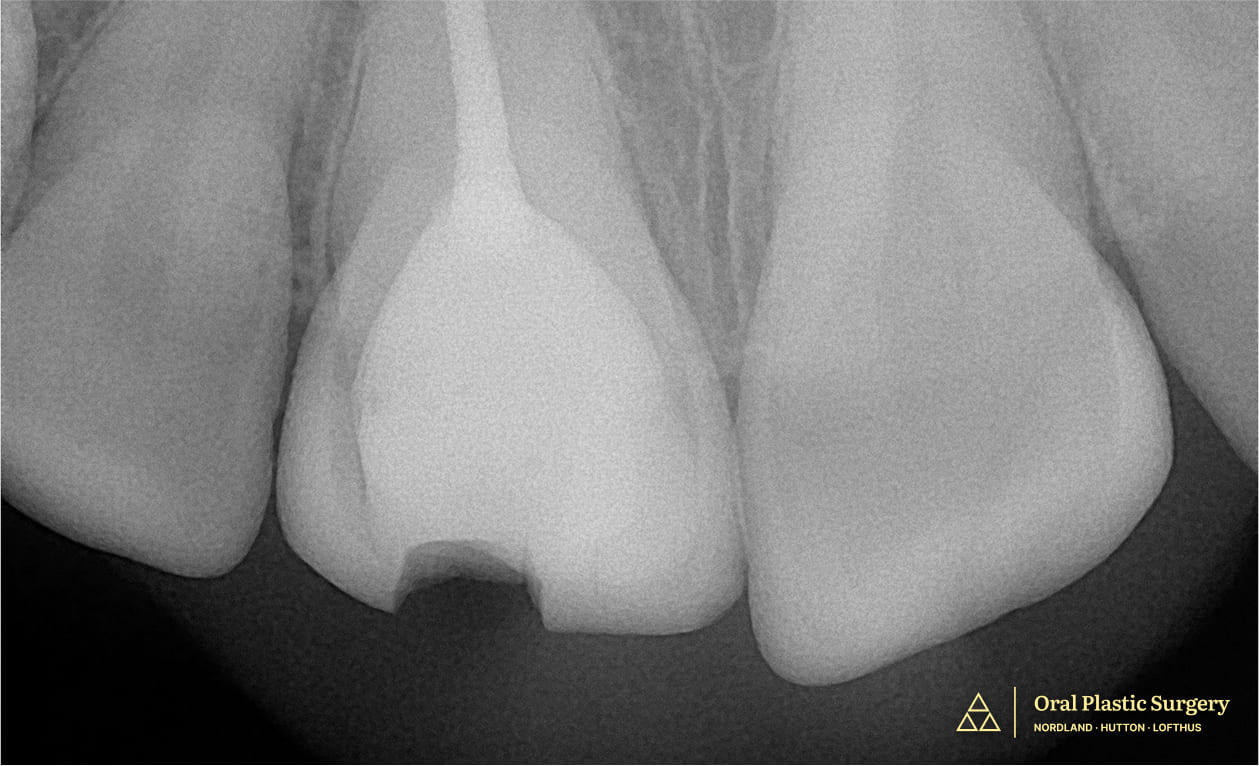

Showing a large filling and minimal natural structure, making the tooth non-restorable

Showing a large filling and minimal natural structure, making the tooth non-restorable.

Tooth #8 shows a visible fracture, indicating structural compromise and the need for further evaluation and treatment